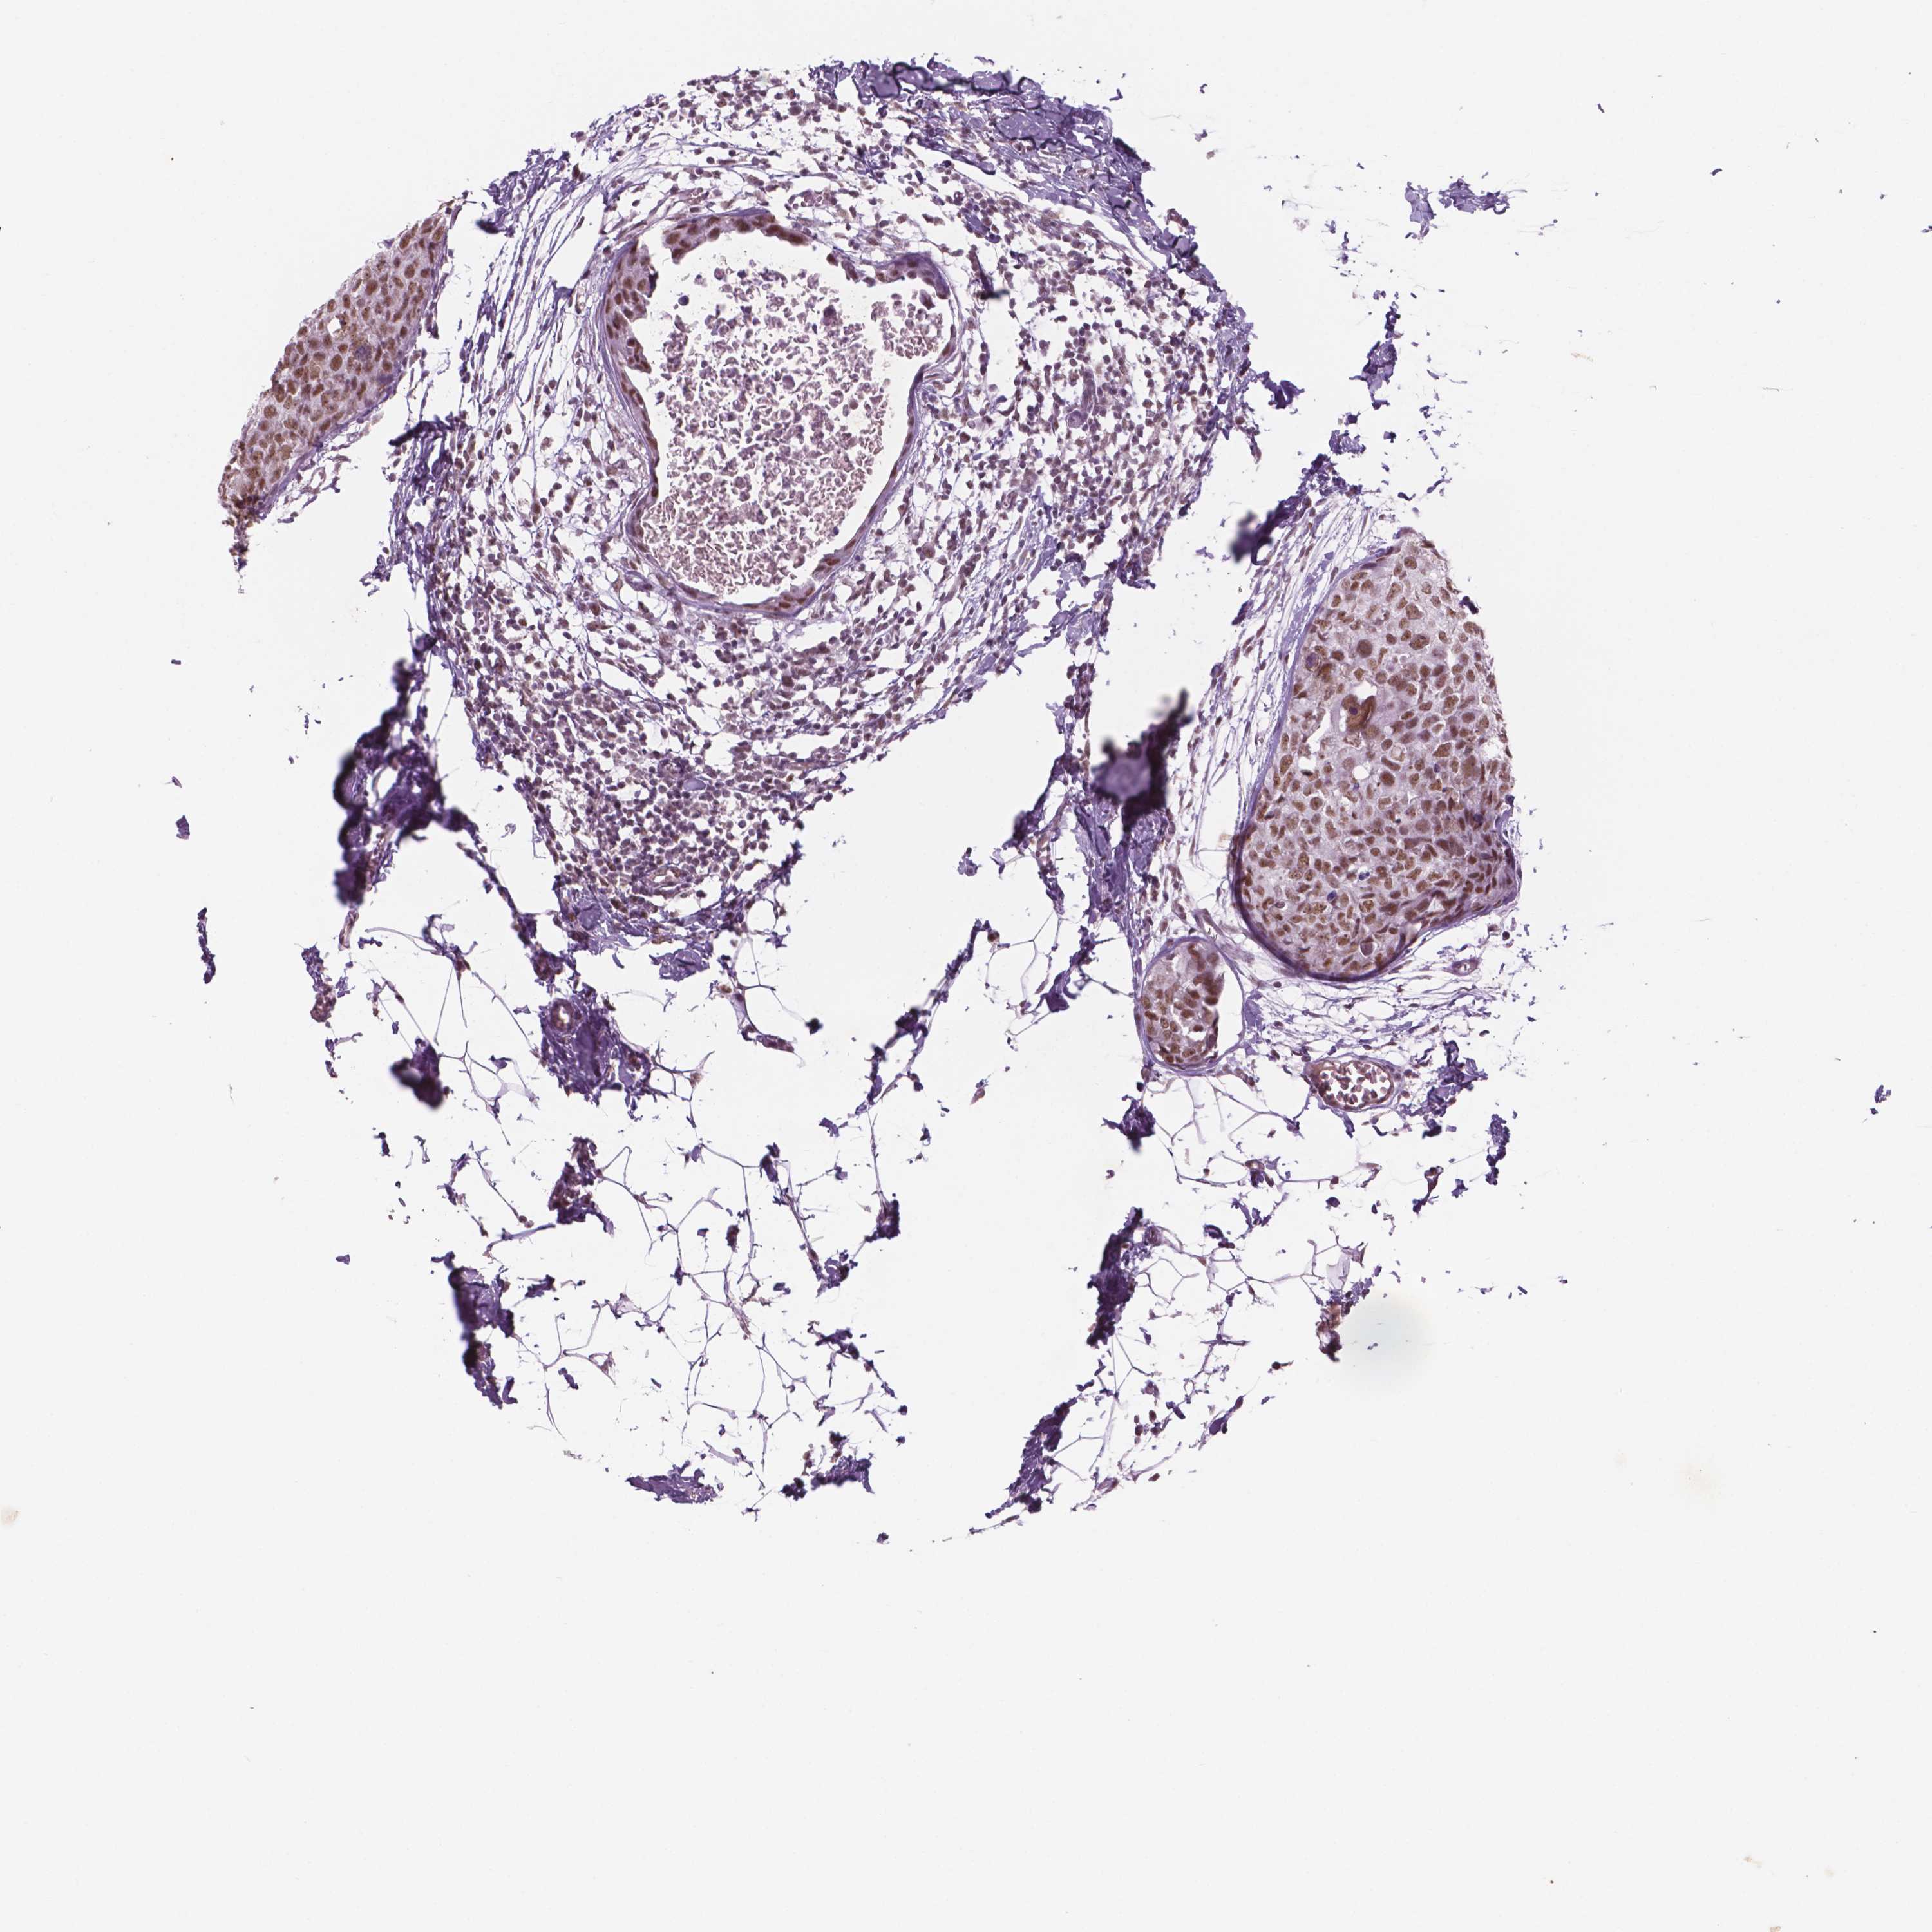

BRCA TCGA BRCA VALIDATION PROTEIN EXPRESSION

ANTIBODIES

AND

VALIDATION